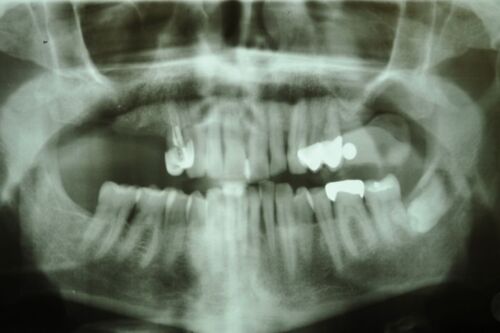

Langjährig rekonstruierter Kieler CMD Patient im Erhaltungsrecall

Inzwischen ist der Patient auch über 80 Jahre alt und seit einem Jahrzehnt aufwändig funktionstherapeutisch versorgt.

Als der Patient sich damals vorgestellt hat lag der Lockerungsgrad der Oberkiefefronzähne bei 2.

Es war nicht klar, ob die Frontzähne erhalten werden können.

Nach parodontaler Vorsanierung und vierteljährlichem Erhaltungsrecall und der funktionstherapeutischen Einstellung der Bisslage, über neu inserierte Implantate im ersten und zweiten Quadranten hat sich die Situaiton des stomatognathen Systems derart stabilisiert, dass die aktuellen Taschentiefen bei entzündungfreien 2 Millimetern liegen.